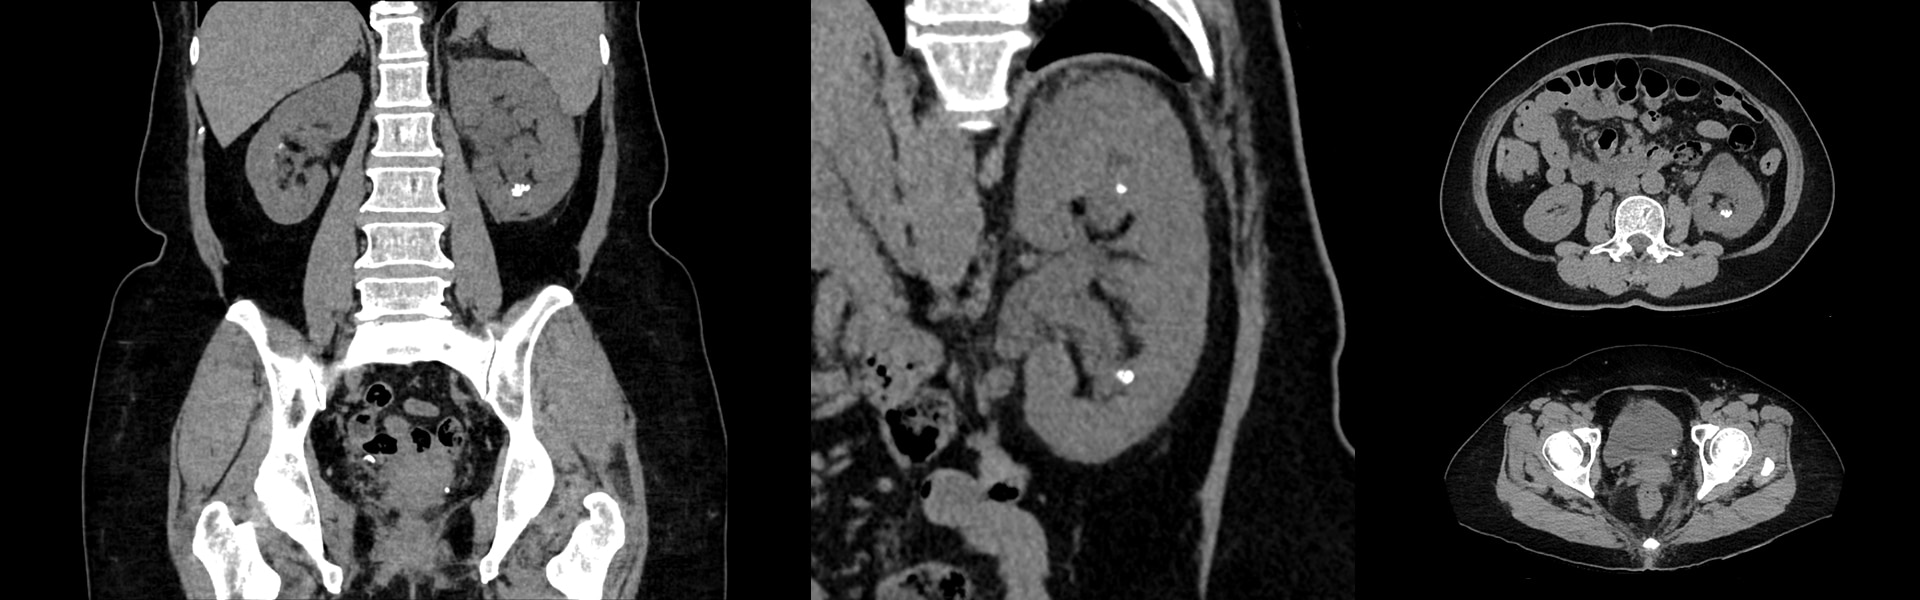

Vea exactamente lo que necesita ver

Imágenes clínicas

La lesión en el oído derecho mide 3,5 mm en el TC. Tumor en la cadera que atraviesa el hueso.

Medición cervical derecha de 6 mm.